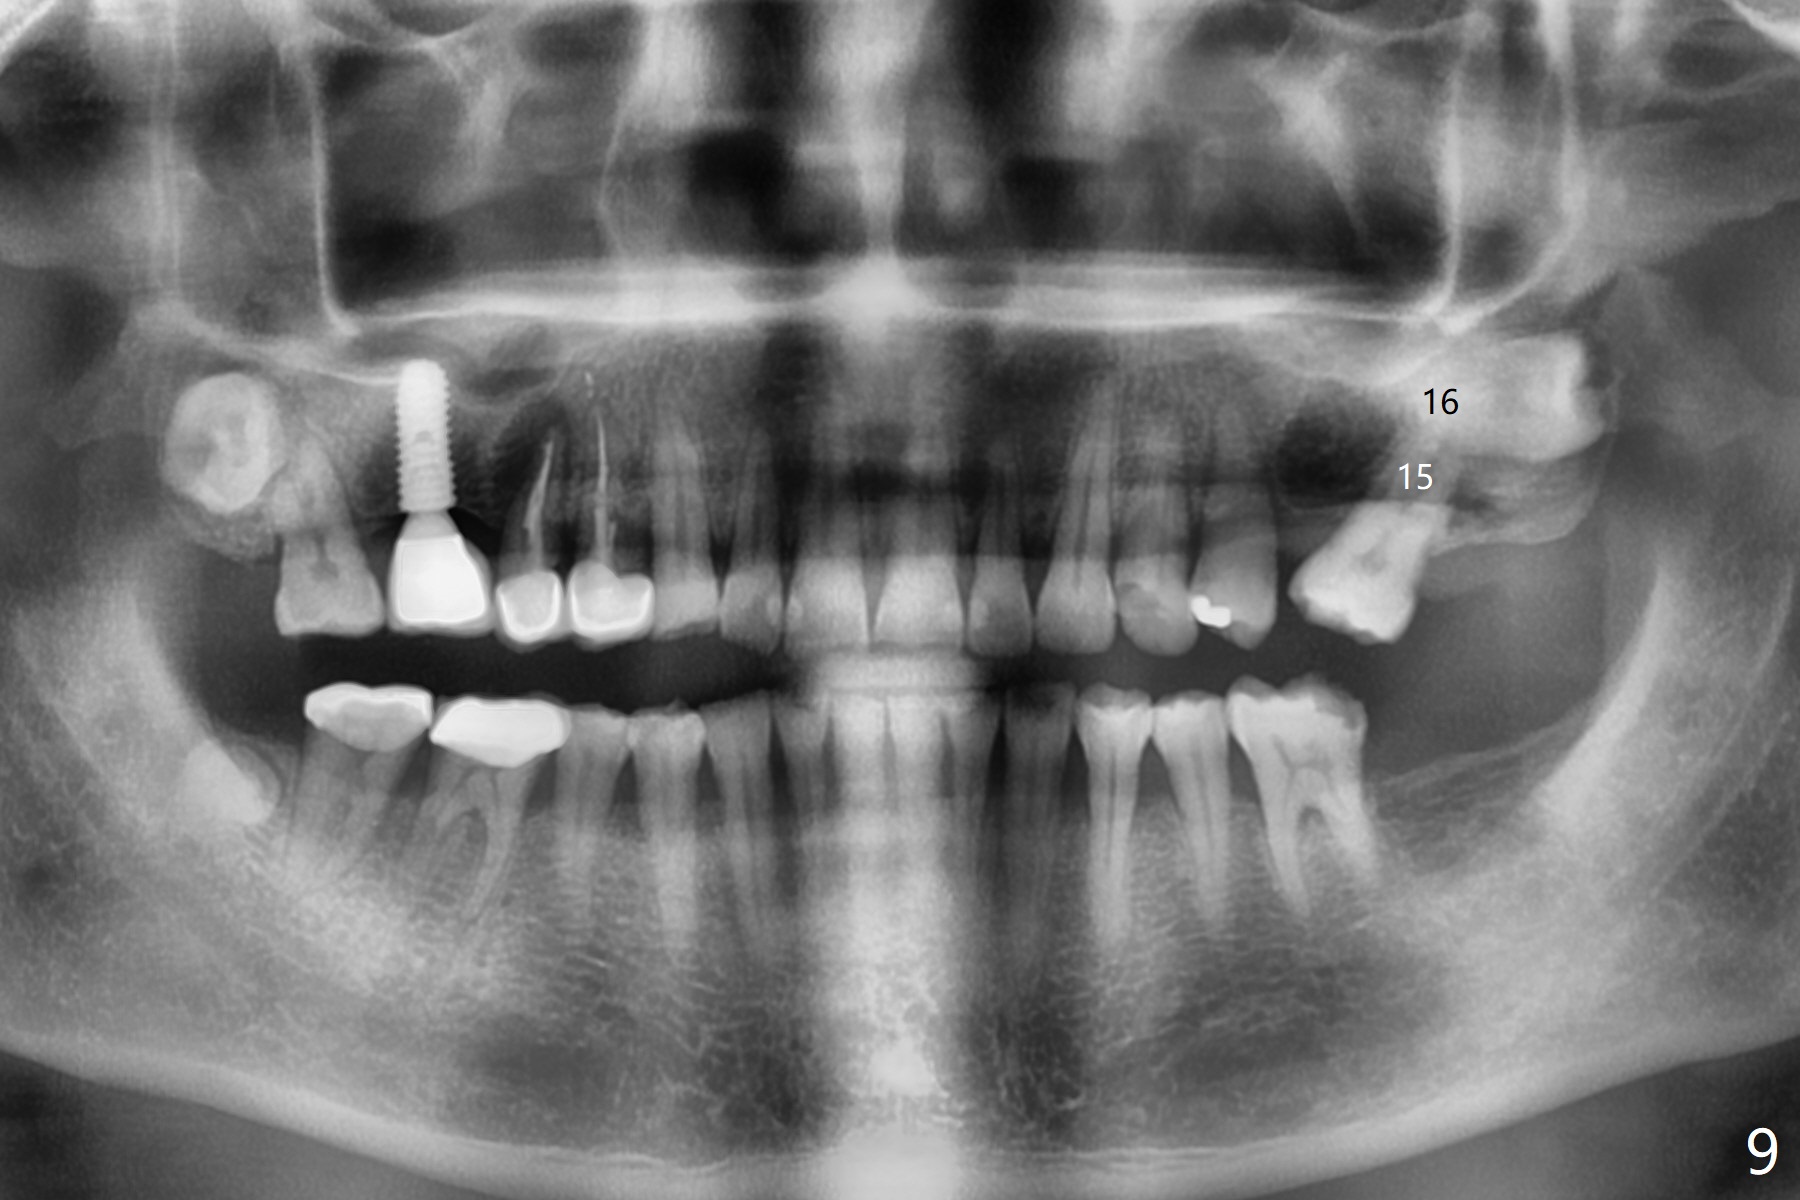

Crown/Implant Ratio

A 53-year-old man has signs of bruxism (Fig.1 diastema *) and root fracture or RCT failure at #4 (Fig.4 (large PARL *)). The RCT failure is related to overload of the affected tooth, which is in turn partially due to infraocclusion of the neighboring implant crown (Fig.1 arrows (implant positioning not ideal)) and partially to due to partial edentulism (Fig.2 missing teeth #14 and 18). For long term, limited ortho will be performed to upright and distalize the tooth #15 (Fig.3 arrow), followed by implants at #14 and 18. For now, the tooth #4 will be extracted (Fig.5), followed by osteotomy in the distal slope of the socket with guide (Fig.6 to get good trajectory). To place a bone-level implant (Fig.7 green), an abutment (blue) with long cuff (pink) is to be used. With poor implant/crown (white) ratio, stress occurs at the junction of the implant/abutment (red arrow), resulting in easy abutment screw loosening. In contrast, stress may be applied to directly to a tissue-level implant (Fig.8 arrow) with less likelihood of abutment screw loosening. The implant/crown ratio improves by approximately 5.5 mm. The roots of the teeth #15 and 16 are so close to each other that interference may occur when the tooth #15 is being uprighted (Fig.9). The empty socket of the tooth #4 is wide buccopalatal (Fig.10); the buccal plate is resorbed coronally (Fig.10 <) so that a 4.5 or 5 mm diameter implant should be placed palatal (Fig.11). Use sticky bone to repair the buccal plate defect and PRF membrane or plug for sinus lift. Following #15 uprighting and distalization, a 5x10 mm implant will be placed at #14; the ridge is triangular (Fig.12 <) so that bone trimmer is needed. A 10 mm long implant will be placed at #18 (Fig.14) to avoid perforating to the submandibular fossa (Fig.13 *).